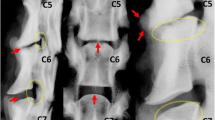

Each specimen was tested in the native state and after surgery. In the T13–L5 specimens, surgery was performed on the L2–L3 IVD. Via a left lateral approach, a small, transverse stab incision was made into the middle of the IVD with a #11 surgical blade. All NP material was removed (nucleotomy) through the annular incision, using a ball-tipped probe and grasping forceps. The L1–L2 IVD was left intact and served as a control. In the L5–Cd1 specimens, surgery was performed on the lumbosacral (L7–S1) junction via a dorsal approach. The dorsal vertebral arch was removed [dorsal laminectomy; Fig. 1a)] as described previously [13], leaving the articular facets intact. Subsequently, nucleotomy of the L7–S1 IVD was performed as described for the L2–L3 IVD, but through a dorsal annular incision (Fig. 1b). The L6–L7 IVD was left intact and served as a control. The structural composition of all surgically removed NPs was examined macroscopically. The NP taken from the NCD discs was gel-like, similar to the NP seen in Thompson grade I IVDs, whereas the NP from the CD discs had a fibrocartilaginous appearance, similar to the NP seen in Thompson grade II IVDs (Fig. 2) [14].

Dorsal view of the L7–S1 segment from a non-chondrodystrophic spine after dorsal laminectomy, showing the laminectomy defect (arrows) and the incision in the dorsal annulus fibrosus (arrowhead) (a). The mucoid nucleus pulposus (arrowhead) was removed (nucleotomy) from the nuclear cavity using a ball-tipped probe (b)

In the present study, the NP of all NCD spines was gelatinous (Thompson grade I), whereas the NP of all CD spines was fibrocartilaginous (Thompson grade II). In the human spine, an increasing grade of IVD degeneration is associated with an increase in segmental ROM, especially in AR [20, 21]. Therefore, comparison of the native spine from CD dogs and NCD dogs could provide novel insights into the effects of IVD degeneration and could be used to assess the validity of the dog as a model of spontaneous IVD degeneration. We initially aimed to make this comparison, using a correction factor for size differences between the NCD and CD dogs based on the transverse area and height of the IVDs in both types of dog. This analysis indicated that the degenerated CD spine exhibited a larger ROM in AR (in line with human studies [20, 21]) and that the NCD, notochordal cell-rich IVD exhibited a larger NZ (data not shown). However, comparison of the NCD spine with the smaller CD spine, using such a correction factor, is problematic because of the non-linearity of the load–displacement behavior of the spines, and differences in the geometry of the facet joints and other spinal structures between the two types of dog. We, therefore, focused on the effects of decompressive surgery on the biomechanical properties of NCD and CD spines, using each spine as an intrinsic control. Decompressive surgery resulted in an increased ROM and NZ, and decreased NZS in all directions of motion in both groups of dogs, as has been reported in humans [12, 22]. However, nucleotomy of L2–L3 resulted in a significantly larger increase in NZ and decrease in NZS in FE, LB, and AR in the CD spines than in the NCD spines, whereas dorsal laminectomy and nucleotomy of L7–S1 resulted in relatively greater increases in the ROM and greater decreases in NZS in FE, LB, and AR in the NCD spines than in the CD spines. These differences indicate that there are substantial biomechanical differences between NCD and CD spines. Apart from differences in the state of IVD degeneration, these differences may be caused by differences in the size/weight of the types of dog, IVD height and size relative to the size of the dog, the facet joint orientation and conformation, and other spinal characteristics [23]. These differences require further investigation.